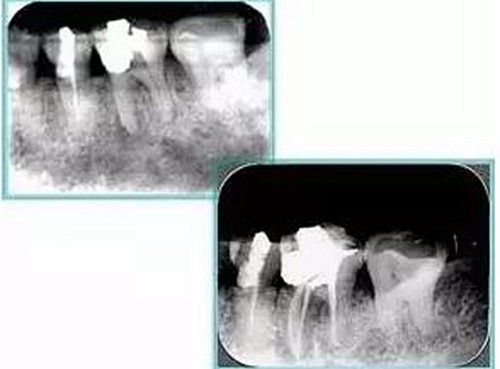

根管預(yù)備步驟包括: ( 1 )橡皮障的使用。 ( 2 )X片共四張 (術(shù)前、診斷絲 、主牙膠尖確認(rèn)、術(shù)后)。

2. X 線片

共有 4 張 X 線片,分別是術(shù)前、診斷絲 、主牙膠尖確認(rèn)、術(shù)后。

( 1 )術(shù)前:術(shù)前 X 線片用來了解牙齒的大概情況。術(shù)前預(yù)期為多根牙時(shí) X 線片應(yīng)偏頭拍攝。

( 2 )診斷絲:根據(jù)術(shù)前 X 線片進(jìn)行開髓、根管的初步預(yù)備后,需要插入診斷絲,用來指示工作器械位置。常用 10 號(hào)或 15 號(hào)擴(kuò)大器作為診斷絲插入牙髓腔。

( 3 )主牙膠尖確認(rèn):通過術(shù)前預(yù)期和診斷絲診斷,明確工作長(zhǎng)度、牙根走向,進(jìn)行根管預(yù)備。之后應(yīng)進(jìn)行主牙膠尖(中銼)確認(rèn),已明確根管是否適合充填。

( 4 )術(shù)后:觀察治療效果。